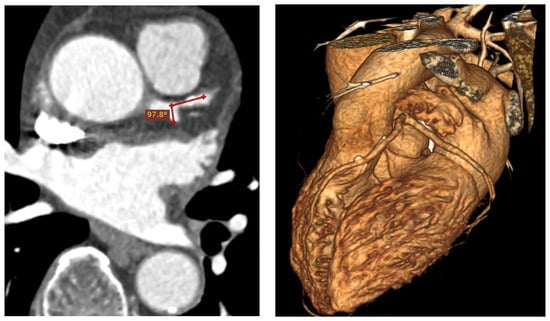

- Temov, K.; Sun, Z. Coronary computed tomography angiography investigation of the association between left main coronary artery bifurcation angle and risk factors of coronary artery disease. Int. J. Cardiovasc. Imaging 2016, 32, S129–S137. [Google Scholar] [CrossRef] [PubMed]

- Sun, Z.; Cao, Y. Multislice CT angiography assessment of left coronary artery: Correlation between bifurcation angle and dimensions and development of coronary artery disease. Eur. J. Radiol. 2011, 79, e90–e95. [Google Scholar] [CrossRef]

- Juan, Y.; Tsay, P.; Shen, W.; Yeh, C.; Wen, M.; Wan, Y. Comparison of the left main coronary bifurcating angle among patients with normal, non-significantly and significantly stenosed left coronary arteries. Sci. Rep. 2017, 7, 1515–1518. [Google Scholar] [CrossRef] [PubMed]

- Cui, Y.; Zeng, W.; Yu, J.; Lu, J.; Hu, Y.; Diao, N.; Liang, B.; Han, P.; Shi, H. Quantification of left coronary bifurcation angles and plaques by coronary computed tomography angiography for prediction of significant coronary stenosis: A preliminary study with dual-source CT. PLoS ONE 2017, 12, e0174352. [Google Scholar] [CrossRef]

- Sun, Z.; Chaichana, T. An investigation of correlation between left coronary bifurcation angle and hemodynamic changes in coronary stenosis by coronary computed tomography angiography-derived computational fluid dynamics. Quant. Imaging Med. Surg. 2017, 7, 537–548. [Google Scholar] [CrossRef]